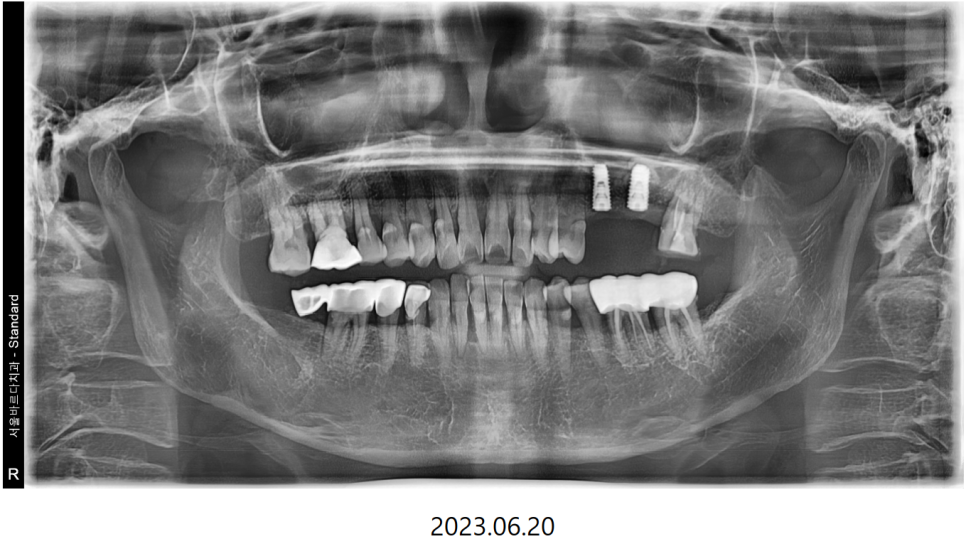

씹을때 먹먹하고 한쪽으로만 식사를 하신다는 이야기를 듣고

전반적으로 뼈와 치아 상태를 확인하는

파노라마 엑스레이를 촬영하여 보니

통증이 있다고 하는 왼쪽 위 큰어금니2개와

바로 그 앞의 작은어금니가 많이 흔들리는 상황이였습니다.